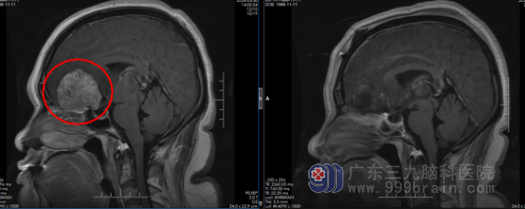

患者手术前后影像对比。

“患者入院时嗅觉全无,右眼视力仅剩光感,呈嗜睡状态。”根据相关影像资料,广东三九脑科医院神经外六科副主任谭家亮发现,阿芸的肿瘤从嗅沟向上生长,对视神经造成挤压,初步诊断是嗅沟脑膜瘤。

4月6日,谭家亮带领神经外六科团队为患者行前颅窝底占位切除术,成功切除大小为4.6cm×4.7cm×4.6cm的肿瘤。术后病理确认脑膜瘤。幸运的是,经过及时手术,近日阿芸的视力和嗅觉都有明显恢复,能够闻到饭菜香味了。